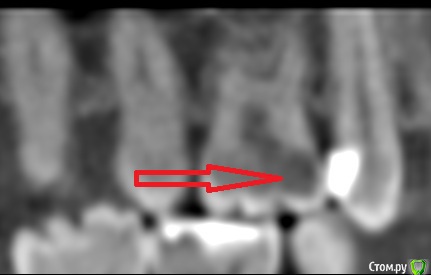

kozloff Опубликовано 18 ноября, 2015 Поделиться Опубликовано 18 ноября, 2015 Подозреваю пульпит зуба 25И к лору не помешает сходить, есть отек слизистой. Гайморита нет. Ссылка на комментарий

Jurai Опубликовано 22 ноября, 2015 Поделиться Опубликовано 22 ноября, 2015 Есть проблема во фронтальном участке верхней челюсти: общая убыль костной ткани, ячеистая структура кости. смещение зубов так, что корни изогнулись, это значит, что либо резорбция (рассасывание) либо очень длительное уже идет воздействие. Могу подозревать новооборазование в этом участке.Вам нужна консультация челюстно-лицевого хирурга-онколога. 1 Ссылка на комментарий